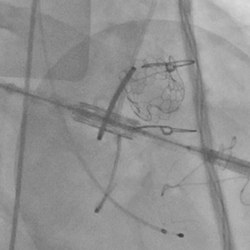

黄焕雷主任带领具有丰富经验的心脏麻醉医师、体外循环师、超声心动图医师、手术室、心外重症监护室、心脏导管室多学科团队,联合心内科专家谢年谨主任,为蔡先生实施小切口下、介入途径的主动脉瓣“瓣中瓣”、二尖瓣“环中瓣”的同期植入手术:黄主任首先在患者左前胸做一小切口,暴露患者的心尖,在跳动的心脏上“绣”上荷包作为介入导管、瓣膜的植入“门户”;随后,黄焕雷主任在超声心动图、放射透视的引导下,将一钢针在患者心尖“扎”入患者心脏内,为之后的瓣膜植入作为引导,具体来说就是将预先选择适合患者大小的生物瓣膜折叠、压缩入细长的输送管道内,好比将瓣膜这一“弹头”安放在输送导管这颗精准制导的“火箭”上,而黄主任的双手则控制这一精准发射和制导,再将瓣膜输送到主动脉合适的位置后释放,新的主动脉瓣便牢固地“卡”在了原有的主动脉瓣架内。经过透视和超声心动图评估,主动脉瓣位置合适,开放、闭合功能良好。随后,黄主任通过这一根钢针和输送导管,利用类似的方式,调整“火箭”的发射轨道,在原有二尖瓣人工瓣环内植入预先选择好大小的二尖瓣生物瓣膜,经过影像学方式评估,新植入的二尖瓣生物瓣工作良好。

球扩释放二尖瓣环中瓣

术后主动脉根部造影